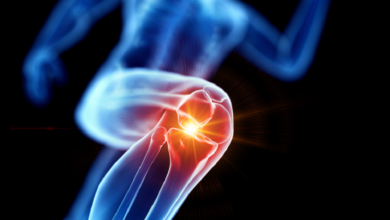

خيوط ذهبية” في ركبتي امرأة كورية تربك الأطباء!

خيوط ذهبية” في ركبتي امرأة كورية تربك الأطباء! كشفت صور أشعة سينية عن وجود مئات الخيوط الذهبية في ركبتي امرأة…